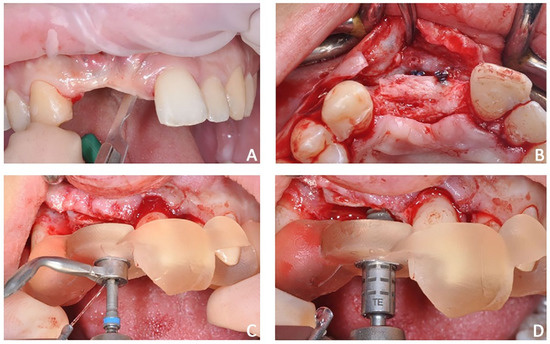

The first part of the therapy consisted of removing the causes of inflammation in the anterior segment, respectively, in the edentulous area removing the fixing screw and around natural teeth by performing professional oral hygiene and scaling (Figure 8B). After that, the treatment plan for implant-prosthetic rehabilitation of the 2.1 was performed and supported by digital systems:

• Prosthetically guided implant planning. After removing the provisional prosthesis, an intra-oral scan was recorded, and the lab technician was asked to produce a virtual wax-up of the ideal position of the teeth. A Cone-Beam Computed Tomography (CBCT) was performed, and the 3D rendered model of the maxilla was registered with the intra-oral scan using the implant planning software Co-Diagnostix (Straumann, Montreal, Canada) (Figure 9). The software was used to plan the implant’s ideal position and design a surgery guide. Figure 10 shows the clinical procedure of the guided implant surgery. Once the osseointegration occurred, an intra-oral scan was performed to register the position of the implant and the surrounding soft tissues with the healing abutment in place (Figure 11A,B).

Figure 10. Case 2. Clinical procedure of the guided implant surgery. (A) flap incision, (B) flap elevation, (C) placement of surgical guide, and (D) guided implant placement.